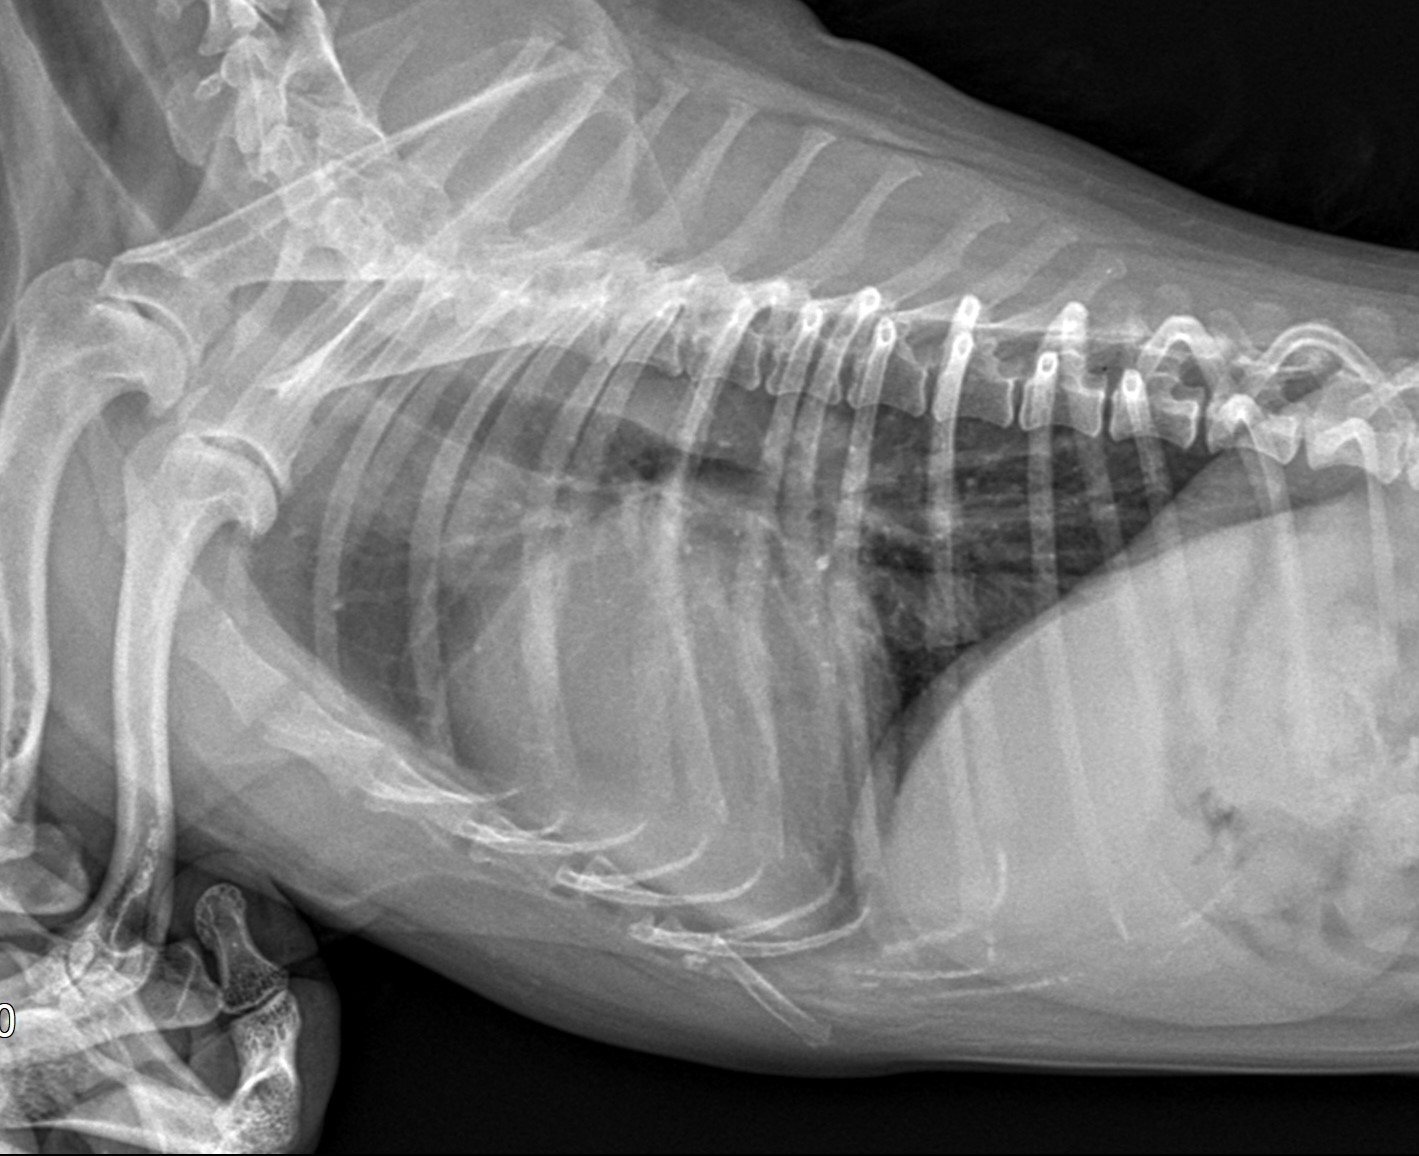

강아지 기관지 협착증숨 가쁨, 호흡 시의 쌕쌕거림, 기침 등은 단순한 감기나 일시적인 증상으로 생각하기 쉽지만, 사실 기관지 협착증이라는 심각한 호흡기 질환일 수 있다. 기관지 협착증은 강아지의 기관이나 기관지가 좁아져서 공기가 자유롭게 이동하지 못하게 되는 상태를 말한다. 이 질환은 호흡 곤란을 유발하고, 심할 경우 폐렴이나 산소 부족 등의 2차 질환으로 이어질 수 있기 때문에 조기 발견과 관리가 중요하다.기관지 협착증은 아직 대중적으로 많이 알려진 질환은 아니지만, 최근에는 반려견의 건강에 대한 관심이 높아지면서 점차 보호자들이 경각심을 가지는 질환 중 하나로 떠오르고 있다. 반려견의 건강을 오래 유지하기 위해서는 질환의 특성을 정확히 이해하고, 사전 예방 및 치료 방법을 알고 있어야 한다. 지금부터..